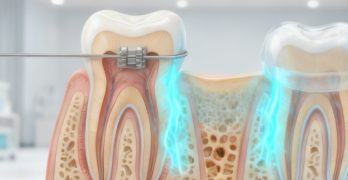

Revisión sobre los vances en los brackets para ortodoncia.

Comenzamos la semana con un artículo llamado Advancement in orthodontic brackets – Review y publicado recientemente en … [Leer más...] acerca de Revisión sobre los vances en los brackets para ortodoncia.